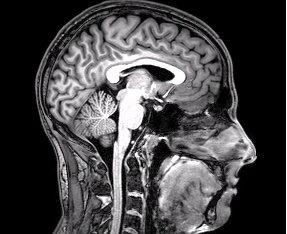

Neuroinfekce. Závažné záněty nervové soustavy a jejich původci

Můžete být sportovec, zdravý jedinec bez častých nemocí, a tudíž máte pocit, že máte silnou imunitu a takto závažný problém se vás netýká. Silná hlava i tělo určitě udělají mnoho, ale někdy jsou bohužel okolnosti proti. Více přitěžujících záležitostí se nakumuluje a oslabí tělo i mysl. Dáte si několik náročnějších tréninků, do toho nedostatečně regenerujete, málo a nekvalitně se vyspíte, nějaké ty stresy v práci nebo v rodině. Tohle všechno v kombinaci s velice důmyslnou schopností některých patogenů pronikat různými tkáněmi, může způsobit, že si otevřete cestu pro novou anebo doposud ve vás dřímající pohromu v podobě infekce, která se dotkne vaší periferní anebo rovněž centrální nervové soustavy (CNS), tedy mozku a míchy. V těle pak vzniká neuroinfekce neboli zánětlivé postižení nervové soustavy.

Pro pořádek si zde jmenujme některé části nervové soustavy, které mohou být napadené a jak se odborně nazývají, jelikož tyto cizí pojmy bývají poměrně běžně používané. Nejvíce laické veřejnosti známé jsou asi pojmy encefalitida, tedy zánět mozku a meningitida, kdy zánět postihuje mozkové obaly. Půjdeme-li ale více do hloubky, vzniknout může například myelitida v souvislosti se zánětem míchy nebo neuritida napadající nervy obecně.

Průnik patogenů do CNS

Před proniknutím patogenů do CNS nás chrání vysoce specializovaná strukturahematoencefalická bariéra. Jedná se o velice živelné prostředí oddělující mozek od oběhového systému. Chrání CNS před jakýmkoliv nebezpečím, a zároveň zajišťuje ovlivnění přenosu vyživujících molekul a neustále se snaží zachovat stabilitu tohoto prostředí. Tak trochu paradoxem je, že zdravá hematoencefalická bariéra je hlavní brzdou ve vývoji léčiv na nemoci CNS. Většina léčiv je touto bariérou vyloučena a do mozku se vůbec nedostane.